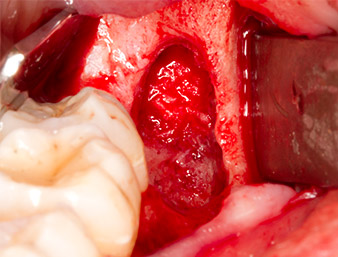

Nach Leitungs- und Lokalanästhesie wurde das Operationsfeld für einen bukkal-retromolaren Zugang weichgewebig eröffnet und dargestellt (Abb. 3).

Das Gewebe über dem Wurzelrest war nicht vollständig verknöchert und bestand zu einem großen Teil aus entzündlich verändertem Granulationsgewebe (Abb. 4).